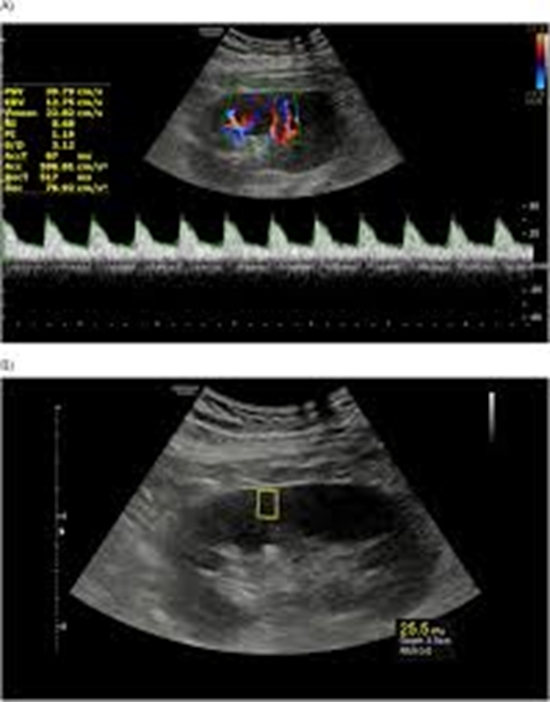

Combination of Doppler US and US Elastography is Superior to Doppler US or US Elastography Alone in Detecting Delayed Kidney Graft Rejection

Objectives: To compare the performance of Doppler ultrasound (US) and US elastography with their combination in detecting delayed graft rejection.

Methods: A prospective cross-sectional study of 60 consecutive adult kidney transplant recipients was done. Patients with creatinine > 1.5 mg/dL and a minimum interval of 3 months from renal transplant surgery were recruited. All patients underwent both Doppler US and US elastography. A direct head-to-head comparison was made. A glomerular filtration rate (eGFR) < 50 was regarded as delayed graft rejection. A resistive index (RI) value ≥ 0.79 was considered abnormal.

Results: RI was more strongly correlated to age, diabetes mellitus, and hypertension with Pearson correlation coefficients of 0.414, 0.390, and 0.386, respectively, while stiffness (kPa) exhibited a stronger correlation to the time period since surgery. Using radiological findings to estimate observed eGFR showed an adjusted R2 of 0.135. Doppler US alone, US elastography alone, and combined Doppler US + US elastography + clinical data, respectively, showed area under curve (AUC) values of 0.668 (95% CI = 0.535 to 0.735), 0.641 (95% CI = 0.507 to 0.761), and 0.792 (95% CI = 0.667 to 0.886) in detecting delayed graft rejection. Estimating RI using clinical and US elastography findings showed AUC of 0.811 (95% CI = 0.689 to 0.901), with sensitivity of 61.5% (95% CI = 40.6 to 79.8) and specificity of 91% (95% CI = 76.3 to 98.1).

Conclusion: Monitoring renal allografts using a combination of Doppler US and US elastography, in conjunction with clinical data, may provide additional early diagnostic and clinical advantages.